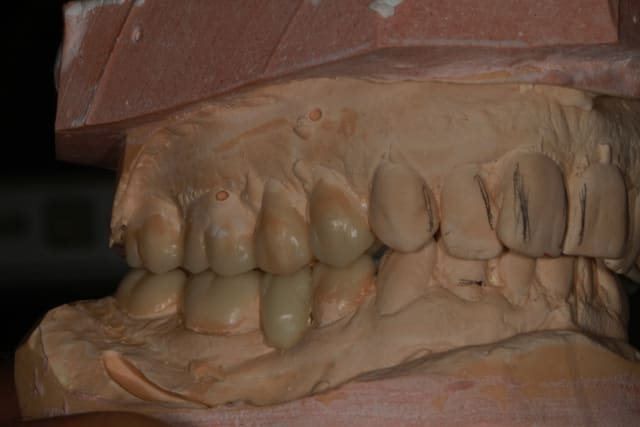

25/09/2013 à 22h10

Wax up et taille crayon...

Empreinte, détourage et préparation des cires avec une occlusion différente de celle du wax up, un peu plus de DV